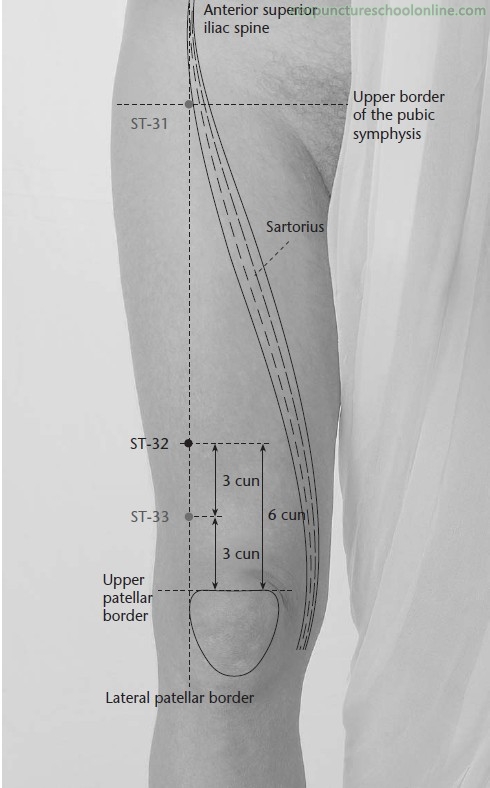

On the thigh, on a line drawn between the lateral border of the patella and the ASIS, in a depression 6 cun proximal to the superior border of the patella, or 1/3 of the distance from the superior border of the patella and the level of the greater trochanter, on the border of the lower and middle thirds.